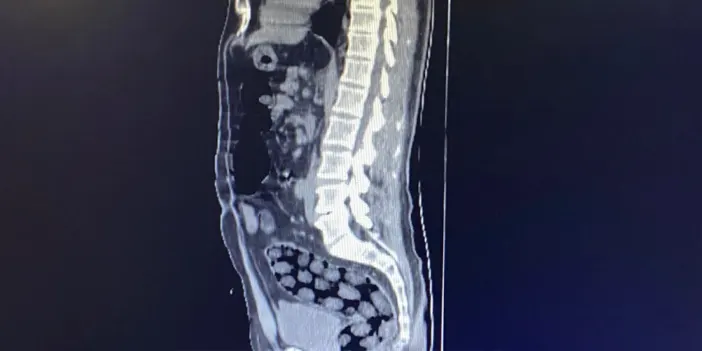

Gözaltına alınan şüpheliler, ifadelerinin alınmasının ardından Bitlis-Tatvan Devlet Hastanesi’ne götürüldü. Yapılan röntgen ve tomografi incelemelerinde, şüphelilerin mide ve bağırsaklarında uyuşturucu madde taşıdığı belirlendi.

91 Paket Halinde Uyuşturucu Ele Geçirildi

Tıbbi müdahaleler sonucunda, şüphelilerin vücutlarından 91 paket halinde toplam 1 kilo 126 gram metamfetamin çıkarıldı. Uyuşturucu maddeye el konulurken, şüpheliler emniyetteki işlemlerinin ardından adliyeye sevk edildi.